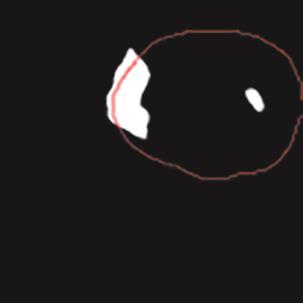

乳腺癌是全球女性最常见的恶性肿瘤之一,准确的病变分割对于乳腺癌的早期诊断与治疗具有重要意义。然而,由于病变形态的多样性以及超声成像机制的复杂性,现有基于深度学习的乳腺超声图像病变分割方法在分割准确性方面仍面临巨大挑战。为进一步提升乳腺超声图像中病变区域的分割精度,该文基于经典U-Net架构,提出了一种新型乳腺超声图像病变分割网络(CWSASKM-BBAM-Net)。首先,在网络中引入逐通道空间自适应选择核卷积模块(CWSASKM),根据不同通道的语义特征为每个空间位置自适应选择感受野大小,以增强多尺度信息的建模能力;然后,引入双向边界感知机制(BBAM),通过融合正向与反向注意力,对目标显著区域及其边界进行协同建模,同时逐步提升对非显著区域与病变区域的区分能力,以进一步强化边界信息的表达;最后,在3组公开乳腺超声图像数据集(BUSI、UDIAT和STU)上开展分割实验。结果表明:该方法在数据集BUSI上的杰卡德指数、精确率、召回率和Dice相似系数分别为71.97%、82.85%、81.40%和80.44%,较次优方法分别提升1.69、1.05、1.28和1.84个百分点;在数据集UDIAT上,这4项指标分别达到78.14%、88.31%、86.73%和86.10%,较次优方法分别提升了2.75、2.04、0.56和2.01个百分点;在外部数据集STU上,该方法也取得了优于其他方法的整体表现。实验结果表明,CWSASKM-BBAM-Net在乳腺超声图像分割任务中展现出更优的整体性能。